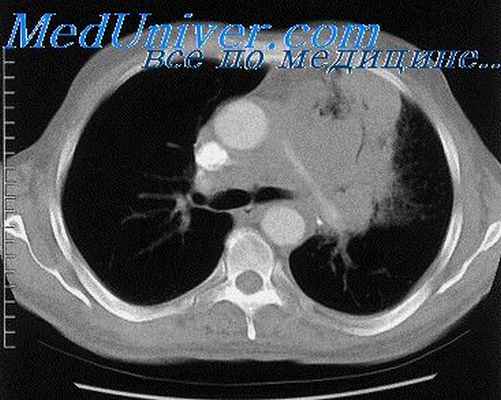

Компьютерная томография (КТ) является более оптимальным методом для диагностики острого медиастинита, кроме того данный метод может быть использован при мониторинге эффективности проводимого эндоскопического или хирургического лечения.

Ядерный магнитный резонанс (ЯМР) предоставляет альтернативу КТ для детей, но он не предоставляет некоторую дополнительную информацию, получаемую при компьютерной томографии [12].

Проводится тщательное рентгенологическое обследование (рентгенография грудной клетки, томография, рентгенография пищевода, пневмомедиастинография). Рентгенологически при медиастините может выявляться расширение тени шеи и средостения, эмфизема средостения, пневмоторакс, гидроторакс, уровень жидкости в средостении, пищеводные свищи.

- компьютерная томография – обнаруживает пузырьки воздуха в средостении;